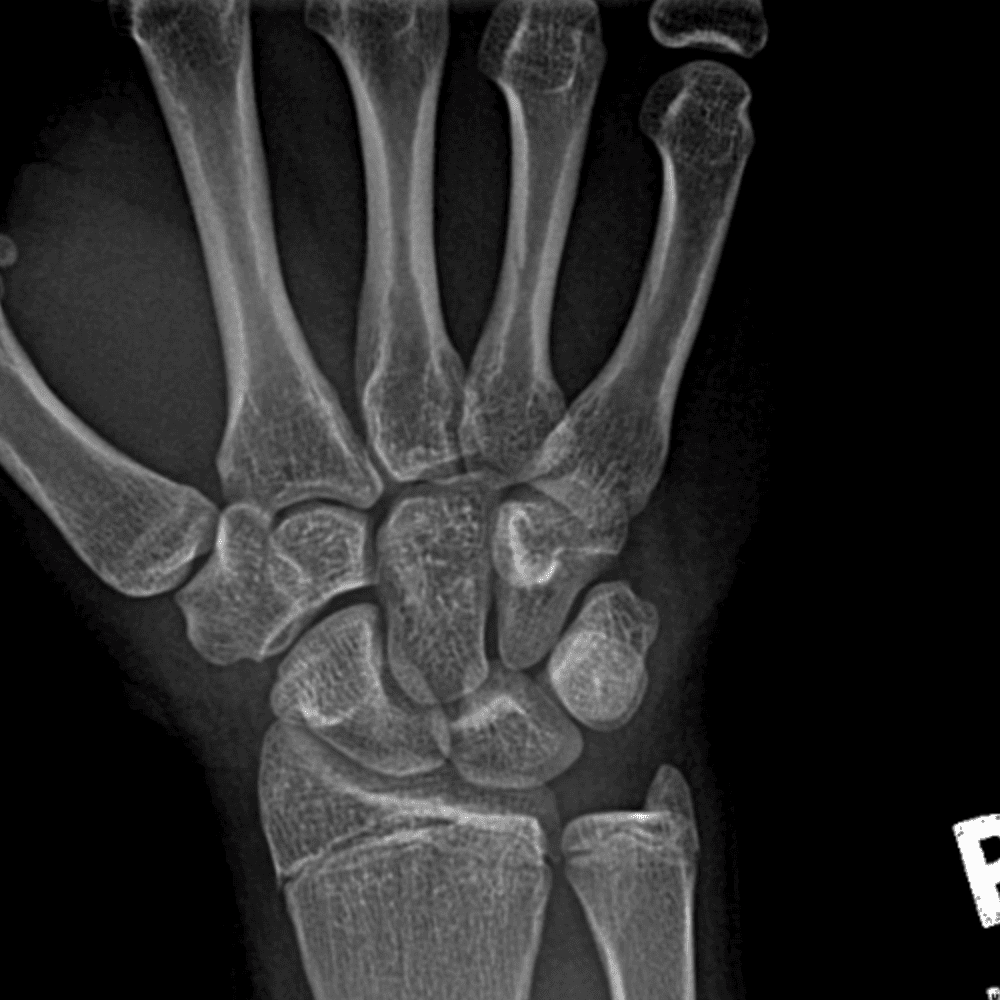

Simulates call by including subtle or difficult cases and some normals.

30 cases